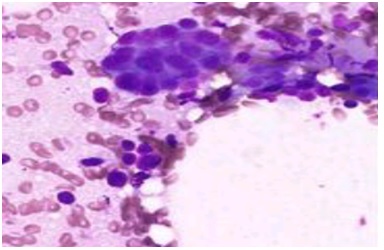

In our study, 4.8% cases had inadequate aspirates and were placed in C1 category which was in concordance with studies done by Sudrat N, et al. [14] whereas Bajwa and Tariq (2010) [15] had a slightly higher rate (13.6%) of C1 cases. An “inadequate” report was issued as due to scanty or a cellular material with in the aspirates, Benign lesionsunder the C2 category were mostcommonly diagnosed with a percentage of 66% (192 cases) was congruent to the study done by Sunita H, et al. [16] andby Ahmed AG, et al. [17]. Fibroadenoma (Figure 1A & Figure 1B) and fibrocystic changes (Figure 2A & Figure 2B) were the most common benign lesion observed in this study similar to that found by Sankaye SB, and Dongre SD (2014) [18]. In this study, atypical lesions in the category C3 comprised of 3% (9 cases) were in agreement to a study done by Sudarat N, et al. [19]. Smears in this category showed ductal epithelial cells benign in nature with overcrowding and mild nuclear enlargement. In the C3 categoryatypical ductal cells of undetermined significance (AUS) was the most diagnosed lesions followed by atypical ductal hyperplasia (ADH). This study showed 5.2% (15cases) in suspicious for malignancy category (C4). Other studies showed variable results in C4 category, namely Bajwa R, et al. [20] in their study found 10.3% in 464 cases and Ibrahim Y, et al.[21] found 13.5% in 66 cases.Smears in this category showed cells. In the category C5, malignant lesions accounted for 21% (61 cases) which was in concordance to the study done by Ibrahim Y, et al. [21]. Invasive ductal carcinoma (figure 3) was the most commonly reported lesionwhich was also found by Bukhari MH, et al.[22].There was a predominance of benign lesions in an age group of 21-40 years and increased malignancy in the age group of 41-50 years. Similar findings were found by Shirish SC, et al.[23] and Almobarak AO, et al. [24].

Figure 3: Invasive ductal carcinoma of breast showing coarse chromatin pattern and intranuclear inclusions (MGG, ×200).